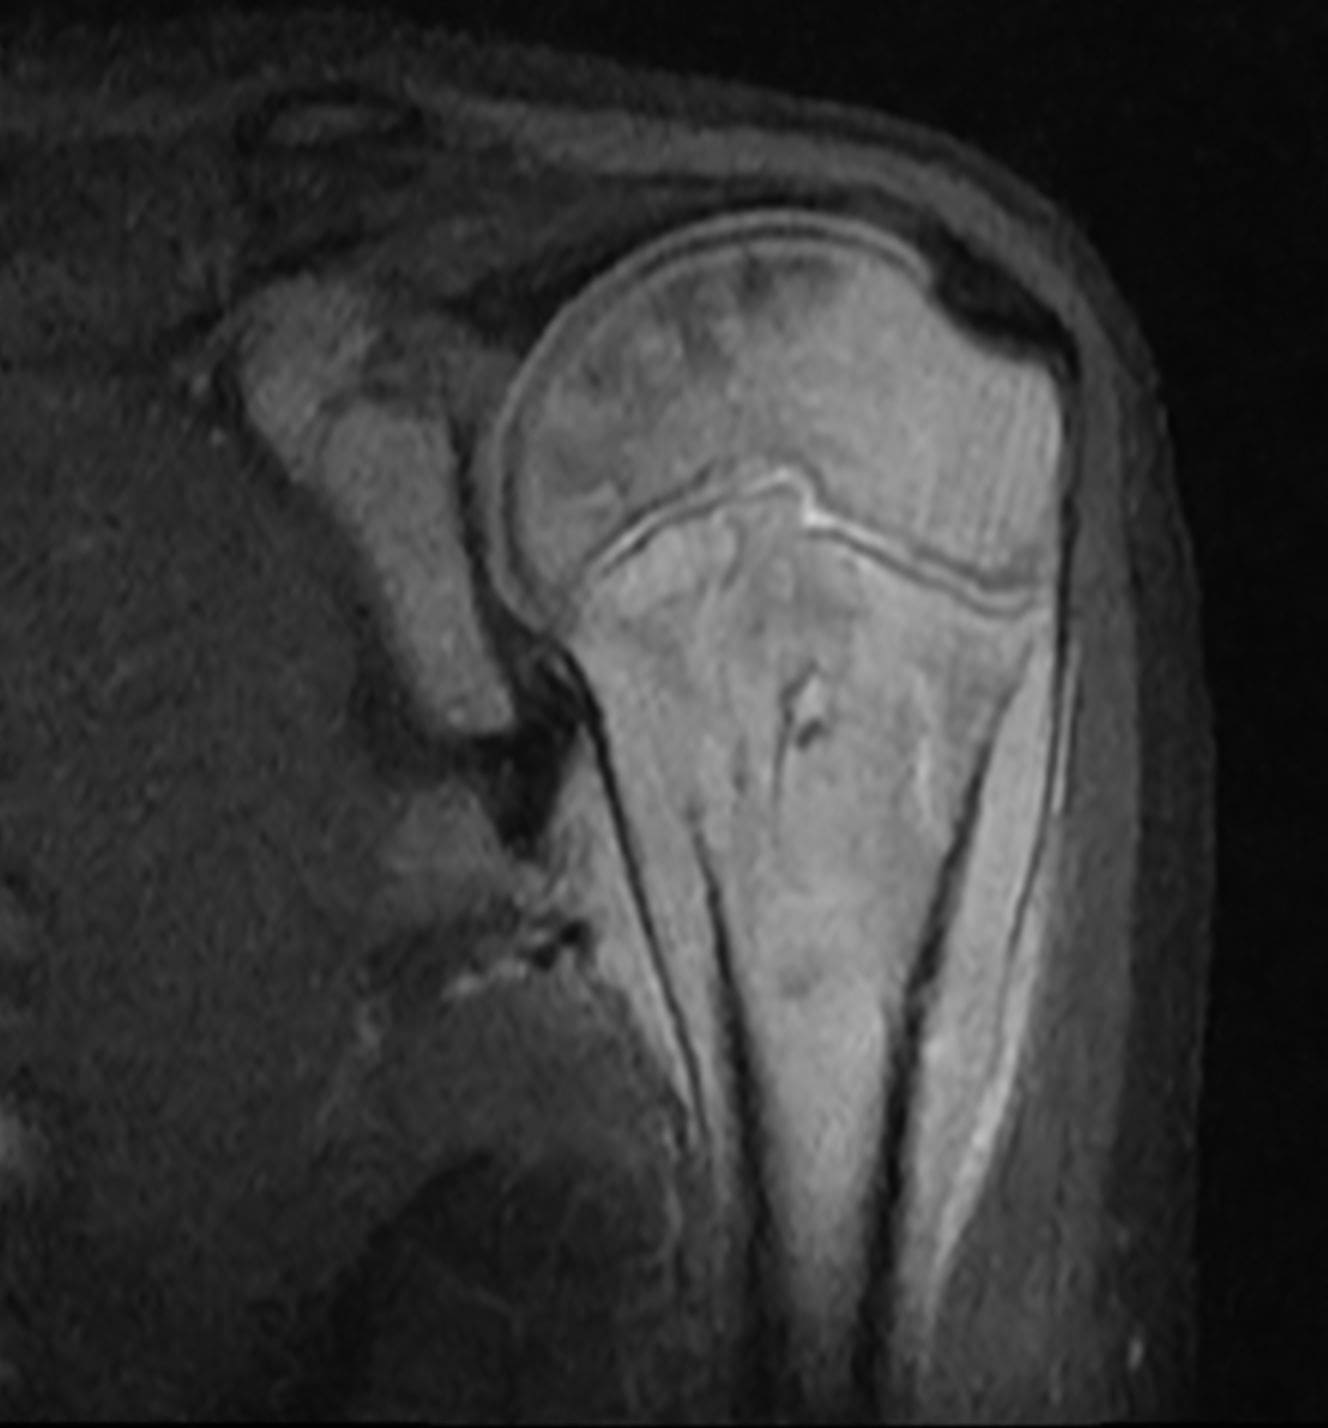

EVAA Radiology provides comprehensive teleradiology services across all subspecialties, with a commitment to excellence and a personal touch—ensuring that referring doctors always have access to a radiologist for discussion whenever needed.

At EVAA Radiology we provide tele-radiology services in the following subspecialties –